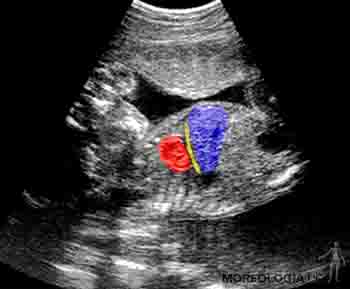

Durante el cuarto mes el feto crece rápidamente, aun cuando el peso se incrementa lentamente, de manera tal que a mediados del período gestacional tiene la mitad de la talla de un recién nacido, pero pesa menos de 500 gramos. Al cuarto mes la piel del feto está cubierta por un vello fino, el lanugo, y son visibles las cejas y el cabello. Ecográficamente en esta etapa es posible identificar el cordón umbilical y visualizar en él la vena y las arterias umbilicales, siguiendo su trayecto en el abdomen del feto (Figuras 2-20a y b).

Figura 2-20a

Figura 2-20b